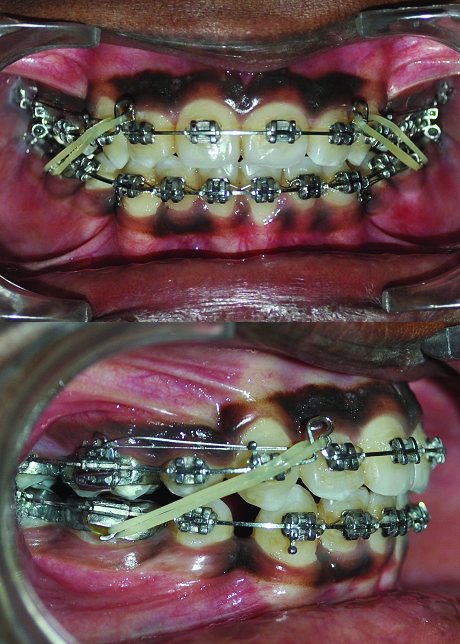

The case was treated using “Hybrid Segmental Mechanics” with extraction of all four 1st premolars with initial segmental retraction of maxillary canines and mandibular right canine using 0.017x0.025" TMA (Titanium, Molybdenum, Aluminum), ‘T-loop’ retraction spring [1,2] [Table/Fig-4a&b]. After segmented retraction of canine, leveling and alignment was carried out using continuous arch sliding mechanics using 0.016" Ni-Ti [Table/Fig-5a-c] and 0.019x0.025" Ni-Ti [Table/Fig-6a-c]. Residual Space closure was achieved using class II elastics [Table/Fig-7a&b]. In mandibular arch, right first molar was protracted to attain class I molar relationship. Finishing and detailing was carried out after closing all spaces. Most of the treatment objectives were met with the treatment, with good intraoral and facial results [Table/Fig-8a-c,9a-e,10a&b,11]. Pretreatment & post-treatment superimposition showed significant dento-alveolar change and good vertical control [Table/Fig-12a&b].

Residual space closure with continuous arch-wire sliding mechanics and class II elastics.